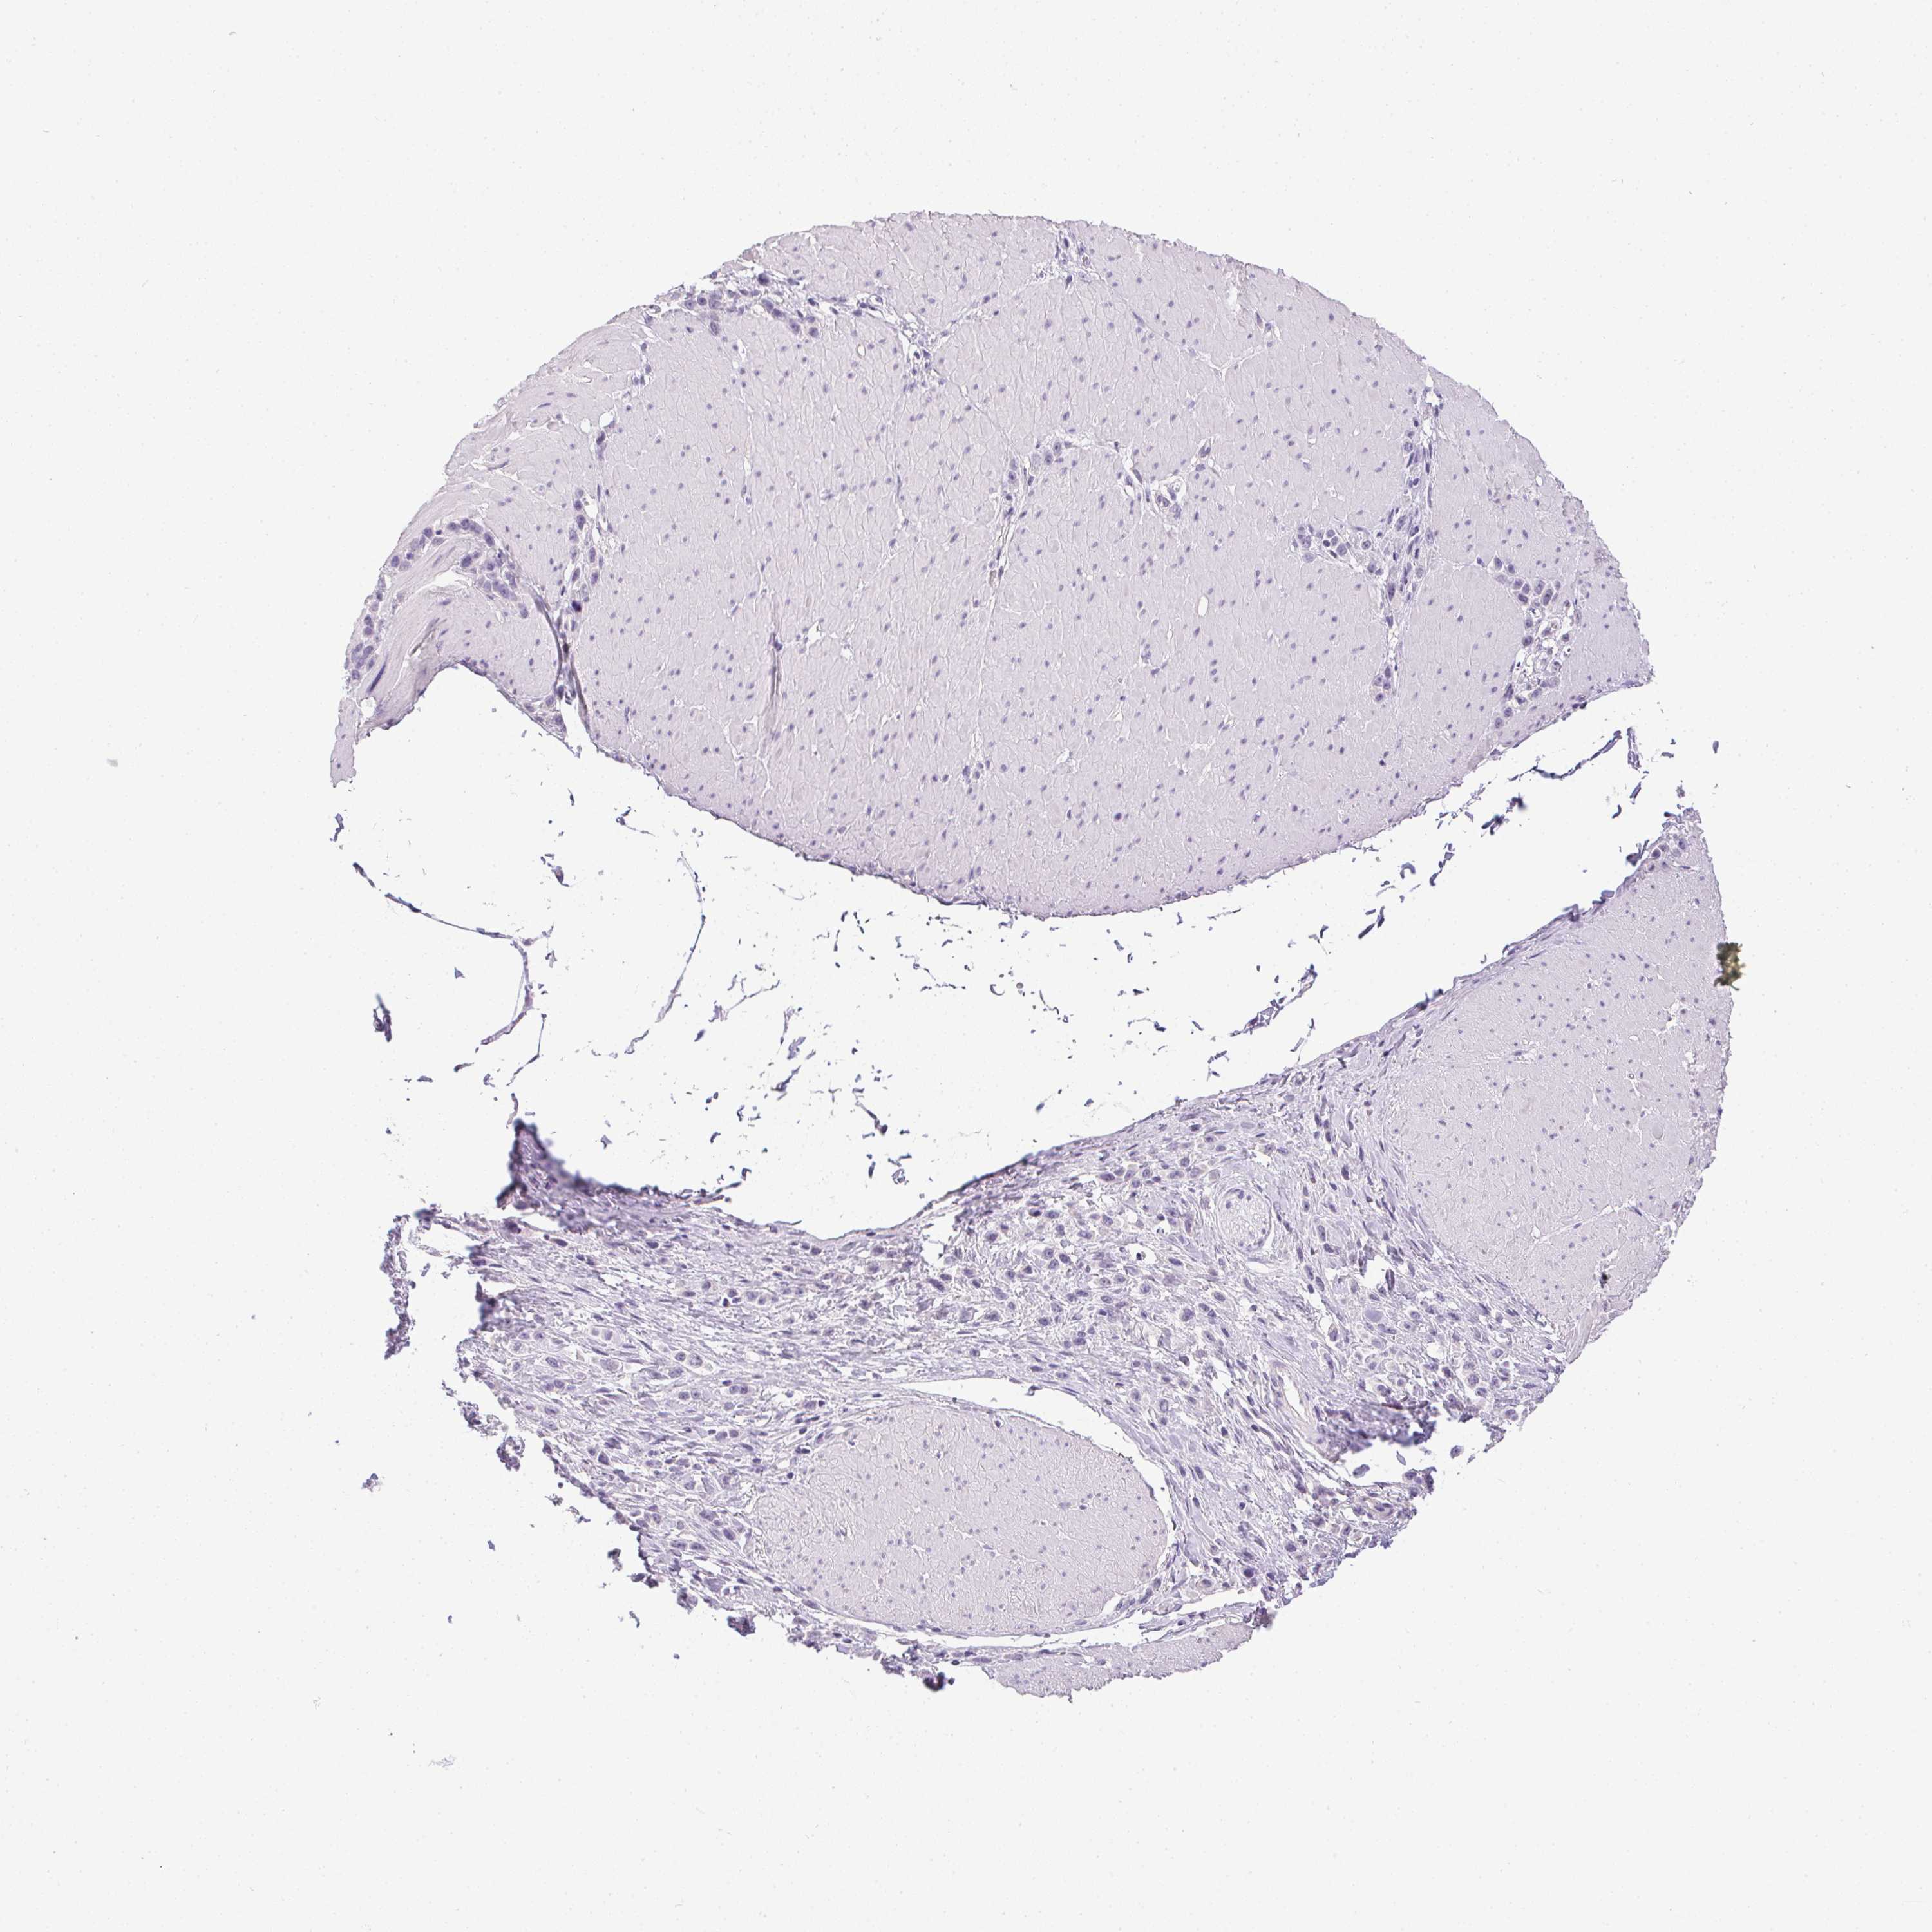

STOMACH CANCER - Protein expressioni

A mouse-over function shows sample information and annotation data. Click on an image to view it in a full screen mode. Samples can be filtered based on level of antibody staining by selecting one or several of the following categories: high, medium, low and not detected. The assay and annotation is described here.

Note that samples used for immunohistochemistry by the Human Protein Atlas do not correspond to samples in the TCGA dataset.

Antibody stainingi

Antibody staining in the annotated cell types in the current human tissue is reported as not detected, low, medium, or high, based on conventional immunohistochemistry profiling in selected tissues. This score is based on the combination of the staining intensity and fraction of stained cells.

Each image is clickable and will lead to virtual microscopy that enables deeper exploration of all samples and also displays staining intensity scores, fraction scores and subcellular localization as well as patient and tissue information for each sample.

Antibody CAB023353

Staining

High

Medium

Low

Not detected

Intensity

Strong

Moderate

Weak

Negative

Quantity

>75%

75%-25%

<25%

None

Location

Nuclear

Cytoplasmic/membranous

Cytoplasmic/membranous,nuclear

Adenocarcinoma, NOS